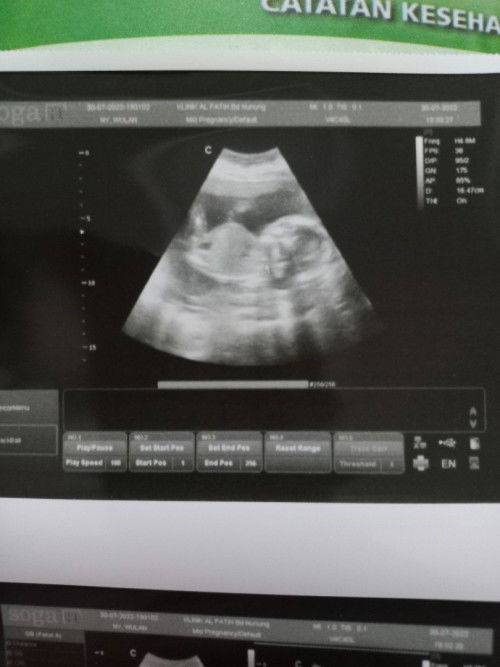

Bunda2 saya mau tanya Dsini ada yg pake kalsiun merk biocal gk? Aku hamil uk 11w, trs pke folamil genio, sma pngen nyoba pake kalsium merk ini. Ini bagus gk ya kira2 Saya blm periksa k doktr, karna 4 mnggu lalu udh k bidan d usg trs masih keliatan kantungnya dan janin masih samar. Rencana k doktr usg awal bulan juli #seriusnanya #bantusharing